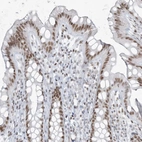

Immunohistochemical staining of human rectum shows moderate nuclear positivity in glandular cells.